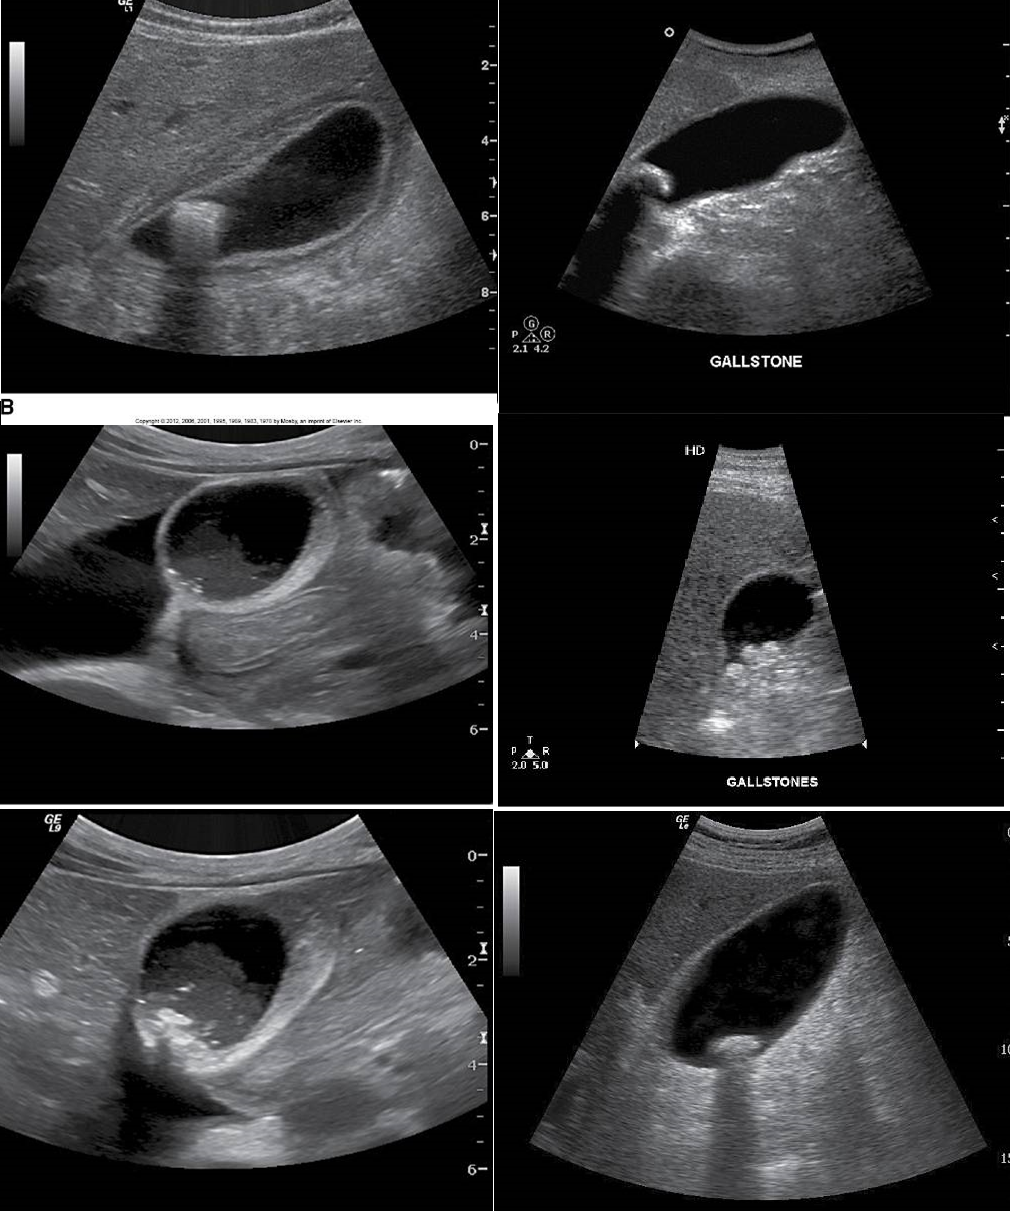

Single, large gallstone or multiple tiny stones

Cholelithiasis

different patterns of cholelithiasis

Rare occurrence - calcium incrustation of the gallbladder wall.

often in older female patients over 60

Associated with gallstones, a form of chronic cholecystitis

Significance: 25% of these patients will develop cancer on the gallbladder wall.

Bright echogenic echo is seen in the region of the gallbladder with posterior shadowing.

The differential will include a packed bag or WES sign.

Porcelain Gallbladder

Cholelithiasis

Cholelithiasis showing multiple small floating and

nonfloating gallstones

Wall Echo Shadow “WES” Sign